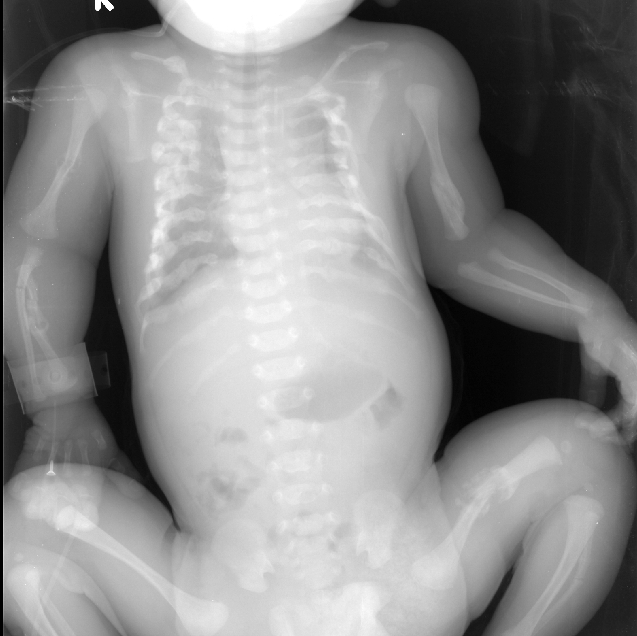

患儿X线片(多处骨折)

2014年的1231日凌晨434分本院新生儿科来了一位特殊的新生儿,患儿整个头颅骨发育不良,触及似棉絮状又或似乎像剥了壳的鸡蛋样的脑袋,患儿左上肢活动可,肌张力稍差,右上肢无力(患儿X线片见尺桡骨骨折有关),不能抬高,也不能平移,双下肢活动能力尚好。完善胸腹x线平片:双侧锁骨中段、双侧多根肋骨、双侧肱骨中段、右侧尺桡骨、左侧股骨、左侧腓骨中段骨折并部分骨折端骨痂形成。

患儿宫内就出现全身上百处骨折,并见肋骨串珠及骨痂生长、头颅骨发育不良,影像学诊断:先天性成骨不全,又称脆骨病,属称瓷娃娃,是一种遗传异质性结缔组织病。其特征为骨质脆弱,是一种由于间充质组织发育不全,胶原形成障碍而造成的先天性遗传性疼痛。其主要缺陷是结缔组织成分发育障碍,表现为骨、巩膜、韧带,甚至是主动脉瓣等胶原纤维发育不良。骨骼改变主要是成骨细胞减少,活力减低,骨样组织生成不良,导致患者软骨及下成骨障碍,骨小梁纤细而分散,骨皮质菲薄,故易发生骨折。轻度在青春期前很少骨折,存活率较高;重度则可胎死宫内。并发症:由于患者长期卧床,可出现坠积性肺炎、泌尿系感染及褥疮等并发症。治疗:无特效治疗,原则是慎防骨折、尽量恢复活动度与功能。在治疗过程中佩戴保护性措施,有效制动骨折端可愈合。目前针对此新生儿的患儿,主要加强护理:睡硬板床,患儿不能由母亲抱于怀中哺乳,以免加重骨折,应由母亲将奶挤出,装入干净的奶瓶中人工喂养。喂养时仍取头高脚低位,头偏向一侧,选择合适的奶嘴,少量多次,谨慎喂养,防止呛奶窒息。详细记录奶量,保证营养供给。在为患儿进行各项操作时都应注意动作轻柔,各项操作集中进行,尽量减少搬动次数。行头皮静脉穿刺时固定手法宜轻,避免重压,造成颅骨骨折。操作后保持患儿肢体处于功能位置。因本病无特效治疗方法,且钙剂、氟化物、维生素C等无疗效,故大多数患者在围产期、婴儿早期或者1岁内夭折。(新生儿 许春莲)